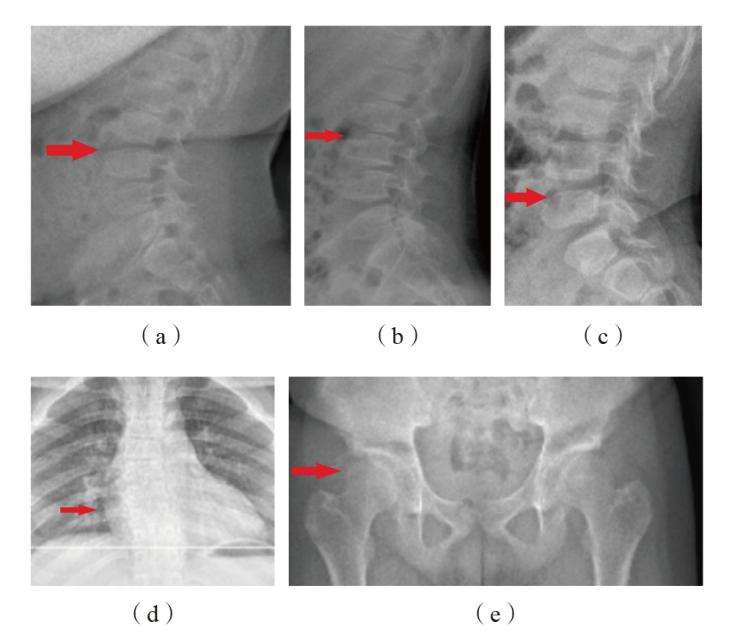

图2 3例SEDT患儿X线检查结果 注:(a)(b)(c)分别为家系1、家系2、家系3中SEDT患儿(先证者)的脊柱侧位X线片,均表现为胸腰椎椎体前部上下缘凹陷、中后部呈驼峰样突起改变;(d)家系2中SEDT患儿(先证者)的脊柱正位X线片,提示胸椎侧弯;(e)家系2中SEDT患儿(先证者)的骨盆正位X线片,提示双侧髋臼缘毛糙、双侧股骨头内侧偏扁。